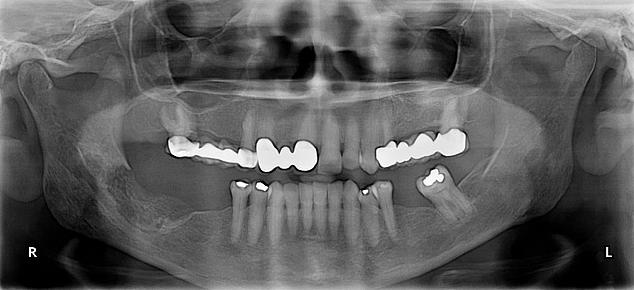

Рентгеновские снимки посттравматического остеомиелита челюсти: Медицинские случаи

Раздел: Образы вокруг